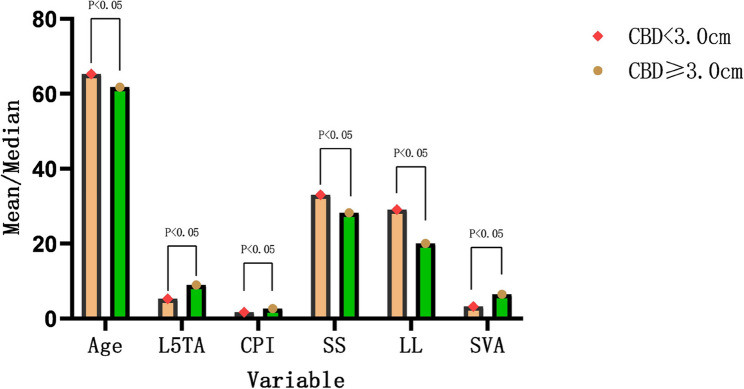

Based on the size of CBD, among the 162 patients, 120 exhibited CB, while 42 had CIB. Univariate analysis demonstrated statistically significant differences in Age, L5TA, CPI, SS, LL, and SVA between the two groups (p < 0.05) (refer to Table 3; Fig. 5). There was no statistically significant difference in gender between the two groups (p = 0.138), and AVR also illustrated no statistically significant difference between the two groups (refer to Table 4).

Table 3: Univariate screening of variables

| CB group(n = 120) | CIB group(n = 42) | t or z | p | |

|---|---|---|---|---|

| Age | 65.33 ± 9.81 | 61.79 ± 9.79 | 2.018 | 0.045 |

| MC(°) | 22.2(16.5 ~ 30.85) | 21.3(16.68 ~ 32.35) | −0.05 | 0.960 |

| FC(°) | 8(3.525 ~ 14.025) | 8.5(3.2 ~ 12.8) | −0.061 | 0.951 |

| BMI(kg/m2) | 23.58 ± 0.30 | 24.55 ± 0.44 | −1.701 | 0.091 |

| Number | 5(4 ~ 6) | 5(4.75 ~ 7) | −1.704 | 0.088 |

| L5TA(°) | 5.3(2.4 ~ 9.1) | 9(6.05 ~ 11.925) | −3.662 | 0.000 |

| CPI(°) | 1.7(0.925 ~ 2.6) | 2.7(1.45 ~ 4.425) | −3.237 | 0.001 |

| AVT(cm) | 1.765(1.0925 ~ 2.4675) | 1.97(0.505 ~ 3.5525) | −0.204 | 0.838 |

| PI(°) | 57.19 ± 12.82 | 53.27 ± 14.50 | 1.65 | 0.101 |

| PT(°) | 22.9(17.925 ~ 28.6) | 25(17.4 ~ 31.05) | −0.612 | 0.541 |

| SS(°) | 33.05(22.925 ~ 41.1) | 28.3(22.15 ~ 36.325) | −2.125 | 0.034 |

| LL(°) | 29.15(16.4 ~ 41.4) | 20.1(6.9 ~ 34.3) | −2.761 | 0.006 |

| SVA(cm) | 3.25(1.3925 ~ 5.585) | 6.525(2.505 ~ 9.9075) | −3.499 | 0.000 |

Abbreviations: BMI Ballistic Missile Intercept, MC Major Curve, FC Fractional Curve, L5TA L5 Tilt Angle, CPI Coronal Pelvic Inclination, AVT Apical Vertebral Translation, LL Lumbar Lordosis, PI Pelvic Incidence, PT Pelvic Tilt, SS Sacral Slope, SVA Sagittal Vertical Axis, Number Number of main curved vertebrae